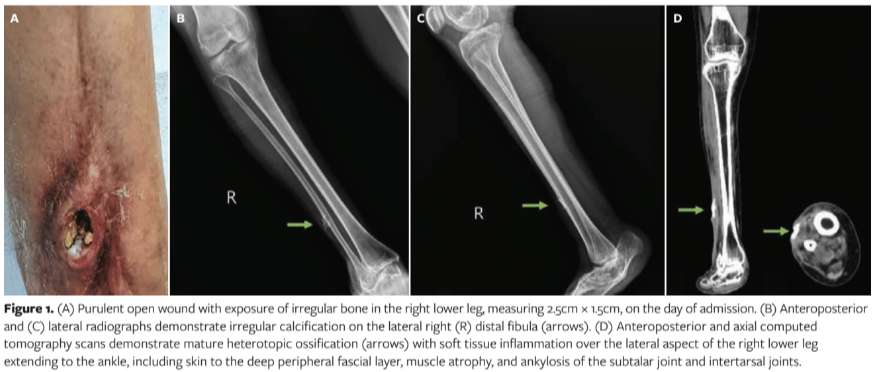

A 49-year-old female with a painful, swollen, and purulent wound, measuring 2.5 cm × 1.5 cm, of the right leg with exposed bone was referred to the authors’ (SJW) clinic after undergoing an unsuccessful 3-month treatment regimen at a local clinic for an open wound of the right leg resulting from a fall from a motorcycle (Figure 1A). The wound was covered with dressings for the first week after the motorcycle injury, followed by open wound care with application of povidone-iodine. The wound seemed improved in the first few weeks; however, infection symptoms emerged approximately 2 months after the motorcycle injury. The patient recalled that her dog had licked the wound several times 1 week after the accident, during the period of open wound care.

The patient’s past medical history included a snakebite (type of snake unknown) on the right leg followed by repeated debridement and skin graft owing to wound complications in childhood. No fever, chills, or other systemic symptoms were evident at presentation to the authors of this case report. An irregular calcification of the lateral right distal fibula was evident on radiographs (Figure 1B, C). Neither white blood cell count, high-sensitivity C-reactive protein level, nor erythrocyte sedimentation rate was elevated according to blood test results. Empirical antibiotic therapy consisting of cephradine 500 mg every 6 hours was prescribed in the OPD. Pus culture was positive for P canis and Pasteurella stomatis. Mature HO with soft tissue inflammation on the lateral aspect of the distal right leg was evident on computed tomography scans (Figure 1D).